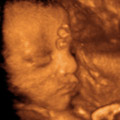

Бремени сте: 30 недели

Плод во 30. недела

Нежните влакненца кои го прекриваа целото тело, сега полека се губат, а коскената срж ја превземала својата работа и создава сопствени црвени крвни клетки кои се грижат за пренесување на кислородот во крвта. Фетусот во оваа фаза пред се расте и добива на тежина. Сега веќе има 1,4 килограм. <